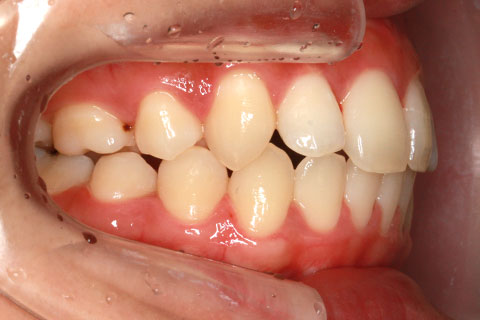

ハーフリンガル矯正4:上の歯のみ舌側矯正で治療(矯正期間24ヶ月)

- 年齢・性別

- 23歳女性

- 治療期間

- 2年0ヶ月

- 抜歯

- 上下4番抜歯

- 治療費

- 110万円

- 備考

- マルチブラケットを用いた矯正治療

- 治療内容

- 施術の副作用(リスク)

- 表側矯正と比較して、前歯のラビッティング(舌側傾斜)を起こしやすい。